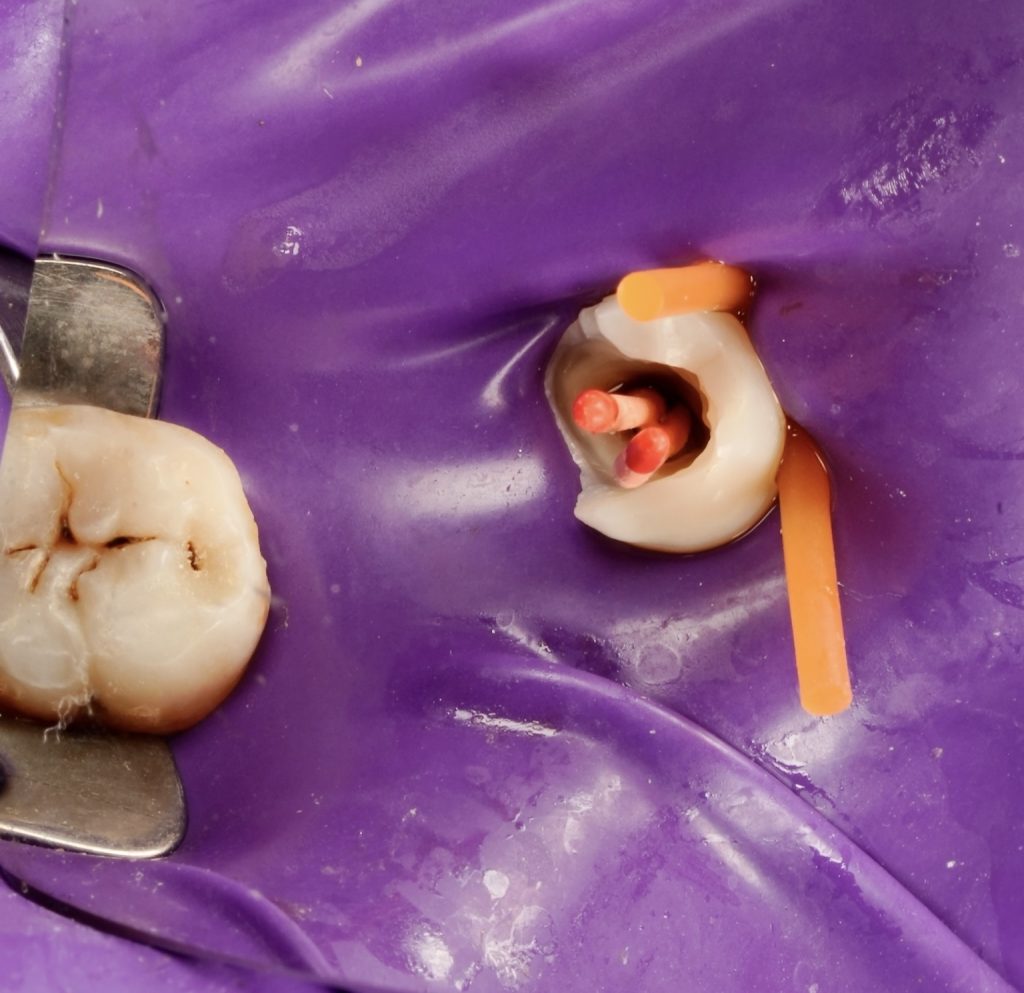

2️⃣ Isolation and Access Cavity Preparation

Rubber-dam isolation achieved, followed by conservative access under a dental microscope (Fig 2). Upon deroofing, a single oval orifice was noted, which bifurcated distally and palatally at deeper levels. Troughing with ultrasonic tips revealed all three canal paths clearly.

- Fig 2: Conservative access cavity under microscope.